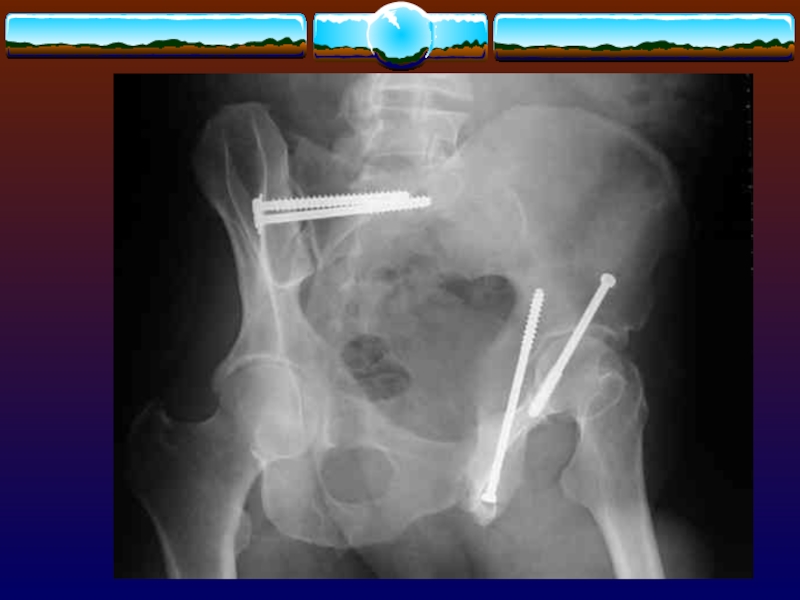

Слайд 110Методики наружной фиксации

Стержневой аппарат

Тазовый зажим Gaza

Методики наружной фиксации Стержневой аппарат Тазовый зажим Gaza

Слайд 111-ограничивает движения

-уменьшает кровотечение из области перелома, а также межостистого венозного

сплетения

-способствует тампонаде, так как восстанавливаются истинные размеры таза и

-ограничивается

объем внебрюшинного пространства

-помогает быстро восстановить мобильность пациента

-не может остановить артериальное кровотечение

-ограничивает движения-уменьшает кровотечение из области перелома, а также межостистого венозного сплетения-способствует тампонаде, так как восстанавливаются истинные размеры